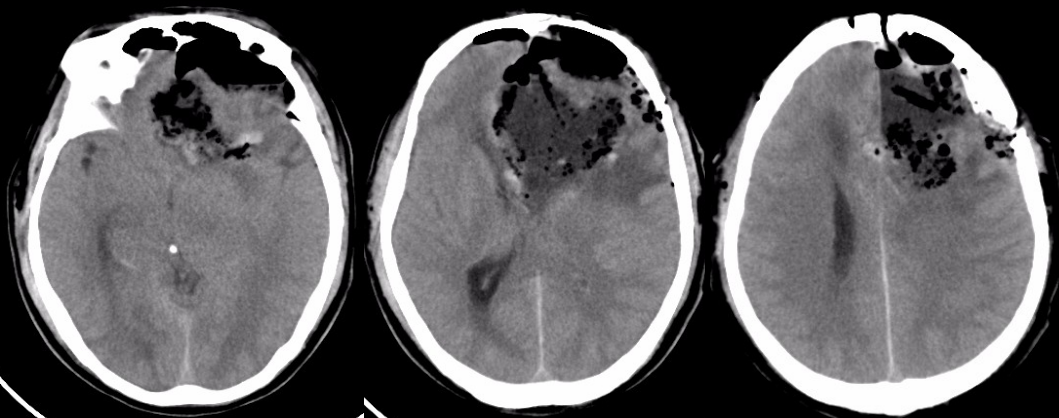

术后头颅CT